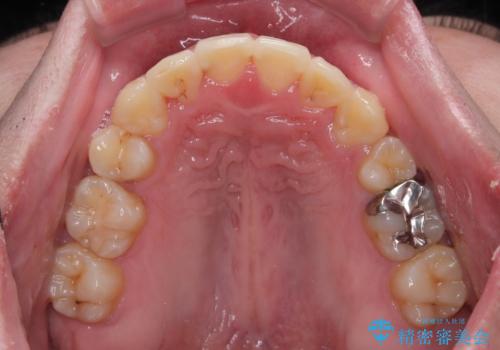

患者様には辛抱強く治療にお付き合いいただき、すっきりとした口元に仕上げることができました。

上下左右の犬歯が八重歯になっており、口元にもやや突出感があるため、上下左右の小臼歯4本を抜歯し、ワイヤー装置にて矯正治療を行うこととしました。